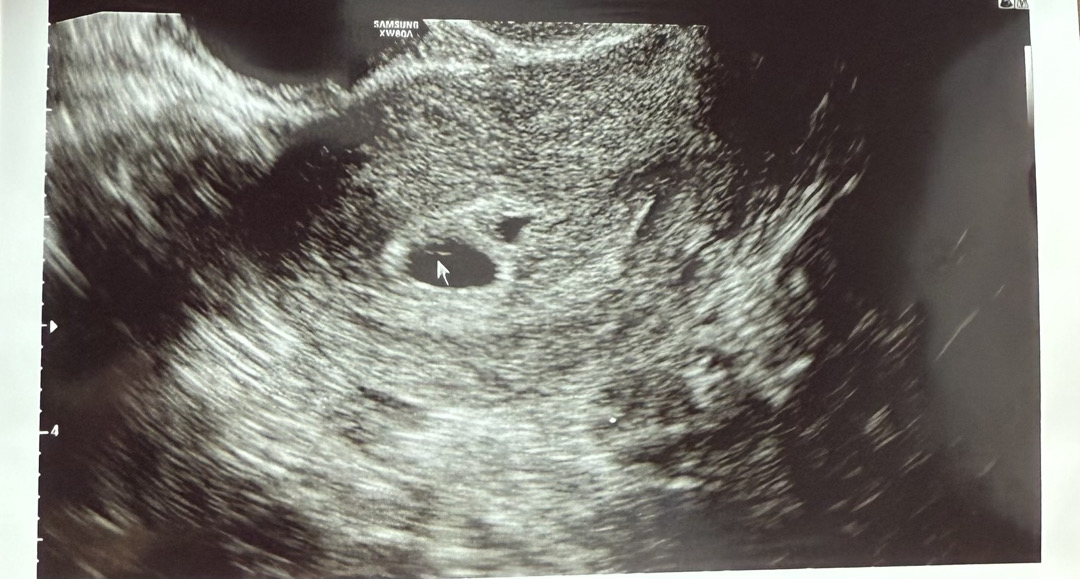

혹시 아기집 몇개로 보이시나요? 임신 극초기이구 , 의사쌤은 4-5주정도 됐을거같다고 하셨어요 근데 하나는 확실한 애기집인데 나머지하나는 출혈일지 애기집일지 10일뒤에 확인해보자고 하셨어요

하나에 피고임이 조금 잇는거 같기도해용 저도 저랫는데 아기집 크기의 30%이상 크기 피고임이면 문제가 되지만 그게 아니여서 괜찮다하셨어요